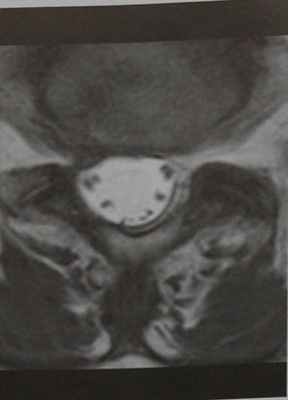

- Сагиттальная проекция (Т1- и Т2-взвешенные изображения, STIR).

- Горизонтальная проекция (Т2-взвешенное изображение).

- Сагиттальная и горизонтальная проекции (Т1-взвешенное изображение с подавлением сигнала от жировой ткани и контрастированием).

Результаты МРТ

Типы:

- Тип I: спайки приводят к формированию конгломератов вокруг нервных корешков.

- Тип II: «пустой дуральный мешок»: волокна конского хвоста формируют спайки с твердой мозговой оболочкой, что создает впечатление «пустого дурального мешка» на срезах в горизонтальной проекции.

- Тип III: на последней стадии воспалительного процесса в дуральном мешке визуализируется мягкотканное объемное образование.

Снимки МРТ позвоночника в Т1-взвешенном изображении:

- Сигнал от ЦСЖ усилен, поэтому наружный контур спинного мозга имеет нечеткие границы.

- Обычно выявляются равномерные линейные, реже узловатые, очаги накопления контраста в оболочках спинного мозга и волокнах конского хвоста.

- В случае заполнения дурального мешка воспаленными мягкими тканями наблюдается диффузное накопление контраста в субдуральном пространстве.

В течение нескольких месяцев после хирургического лечения грыжи диска LIV—LV больного беспокоят усиливающиеся боли в ногах, а также задержка мочи. При клиническом обследовании выявлены седловидная анестезия и наличие остаточной мочи. Повышен уровень маркеров воспале¬ния. МРТ поясничного отдела позвоночника (сагиттальная проекция, Т2-взвешенное изображение). Волокна конского хвоста неразличимы; в позвон¬ках LV-S1 определяется отек.

МРТ поясничного отдела позвоночника (сагиттальная проекция, Т1-взвешенное изображение с контрастированием). Утолщение волокон конского хвоста и накопление контраста в диске LIV—LV, ранний спондилодисцит LV-S1.

МРТ позвонка LIV (горизонтальная проекция, Т2-взвешенное изображение), волокна конского хвоста спаяны с твердой мозговой оболочкой, что создает впечатление «пустого дурального мешка» (тип II).

МРТ позвонка LIV, (горизонтальная проекция, Т2-взвешенное изображение). Нормальная структура волокон конского хвоста.